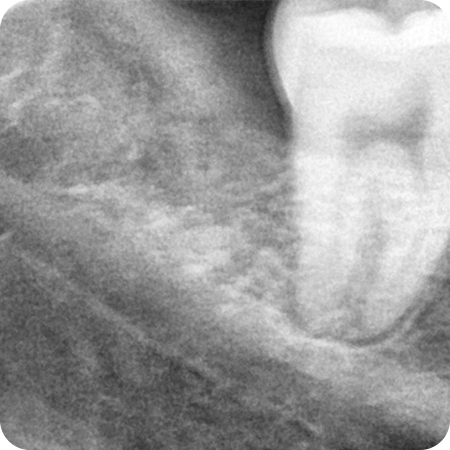

CASE 01

치경부마모 레진 치료

치아 시림 증상으로 내원하셨고

치경부가 굴곡 파절된 환자분

치경부 날카로운 부분을 정리하고

레진으로 파여 있던 부분 충전하였으며

시림 증상도 완화되었습니다.

치료기간 : 2020.07.28 ~ 2020.07.28